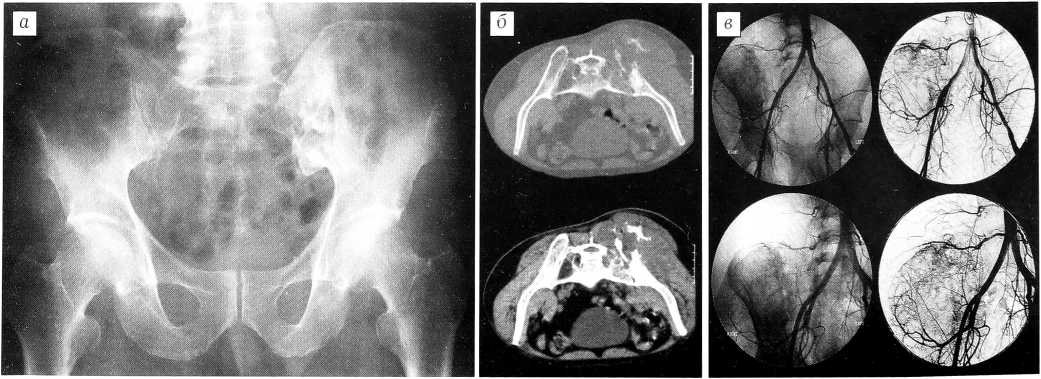

Больной П., 37 лет. За 1 год 2 мес до поступления появились боли в правой ягодичной области, которые связывал с незначительной травмой. Лечился у невропатологов физиотерапевтическими методами. Боли нарастали, и после дополнительного обследования диагностирована хондросаркома костей таза. Больной признан неоперабельным из-за распространения опухоли в область ягодицы и на крестец.

При обследовании в нашей клинике определяется больших размеров плотная опухоль, занимающая область крестцово-подвздошного сочленения и большую часть ягодицы. Размер пальпируемой части опухоли 20x20 см. Рентгенография, компьютерная томография и ангиография: в крыле правой подвздошной кости и правой боковой массе крестца очаг деструкции преимущественно остеолитического характера, неоднородной структуры за счет наличия более плотных участков, с мягкотканным компонентом в ягодичной области. Контуры очага и замыкательных пластинок крестцово-подвздошного сочленения нечеткие. Отмечаются мелкоочаговые разрежения структуры в видимых отделах правой бедренной кости, лонной и седалищной костях (рис. 4). В легких патологических изменений не выявлено.

Рис. 4. Рентгенограмма (а), компьютерная томограмма (б) и ангиограмма (в) больного П. Хондросаркома таза.

Несмотря на широкое распространение опухоли на область ягодицы и характер процесса, учитывая отсутствие альтернативных методов лечения, решено предпринять попытку межподвздошно-брюшной экзартикуляции с резекцией крестца.

11.01.00 больному произведена операция. Из разреза, начатого от уровня остистого отростка L2 позвонка, идущего вдоль всего гребня левой подвздошной кости до передней верхней ости и вдоль паховой связки, а затем продолженного на передневнутреннюю поверхность бедра до его средней трети, осуществлен широкий внутритазовый доступ. Выделены сосуды от общей подвздошной артерии до средней трети бедра. Внутренняя подвздошная артерия перевязана и пересечена. Пересечены и отделены поясничные мышцы, прикрепляющиеся к крестцу и гребню подвздошной кости, а внутритазово — пояснично-подвздошная мышца на уровне крестцово-подвздошного сочленения. Пересечены нервные корешки, формирующие левый седалищный нерв, а также бедренный нерв. Кожный разрез проведен по паховой складке до соединения с разрезом на бедре. Пилой Джильи, проведенной вокруг боковой массы крестца, пересечен крестец на границе его боковой массы и тела. В разрезе была видна твердая мозговая оболочка, которая оставалась неповрежденной. В зоне пересечения крестца опухоль не была вскрыта. Для закрытия раны, занимавшей всю тазовую и ягодичную область и левую половину брюшной полости, сформирован кожно-фасциально-мышечный лоскут с включением в него четырехглавой и части приводящих мышц бедра, васкуляризация которых осуществлялась наружными бедренными сосудами, пересеченными в средней трети бедра. Сформированный лоскут был подшит к крестцу и закрыл рану целиком. Гистологическое исследование опухоли: миксоидная хондросаркома с разрушением подвздошной кости и распространением на большую часть ягодичных мышц. В зоне пересечения препарата опухолевых клеток не обнаружено.

Послеоперационный период протекал без осложнений, рана зажила первичным натяжением. Некроза краев кожного лоскута не было, что свидетельствовало о его достаточном кровоснабжении. Исход у этого больного пока трудно прогнозировать. Существует опасность как рецидива, так и отдаленных метастазов.